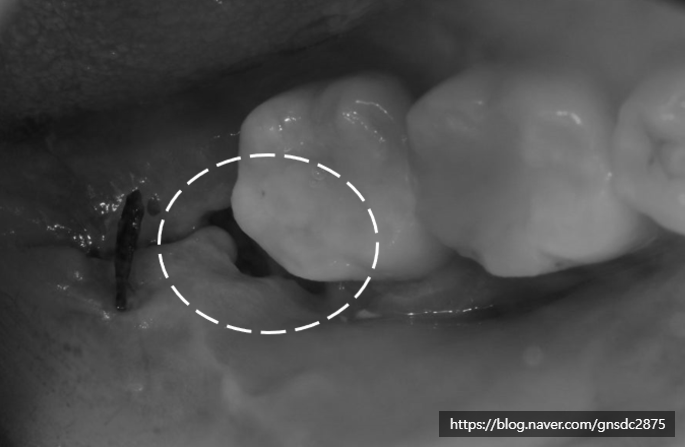

발치 일주일 후 (실밥제거)

✅일주일 후 치과검진 (상태확인)

발치 후 약 일주일 후에는

발치 부위 상태를 확인하기 위해

꼭 치과에 다시 방문하여야 합니다.

실밥이 있다면 실밥을 제거하고

소독을 진행합니다.